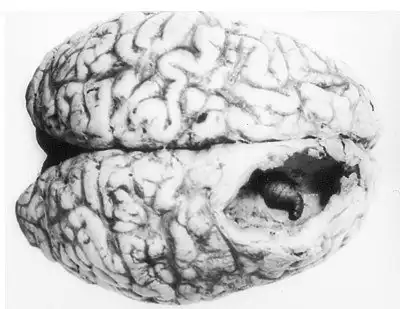

5) Оводовые (Gasterophilidae) откладывают личинки под кожу млекопитающих, в том числе и человека. В Центральной и Южной Америке обитает человеческий кожный овод, который откладывает яйца на москитов. Когда москит садится на покровы тела человека, личинки кожного овода "вбуравливаются" в кожу. С током крови, они могут путешествовать по всему телу и даже проникать в мозг сквозь гематоэнцефалический барьер. Выедая жизненно-важные участки мозга, личинки овода могут привести к смерти.